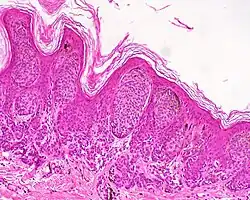

Lentiginous melanocytic naevus